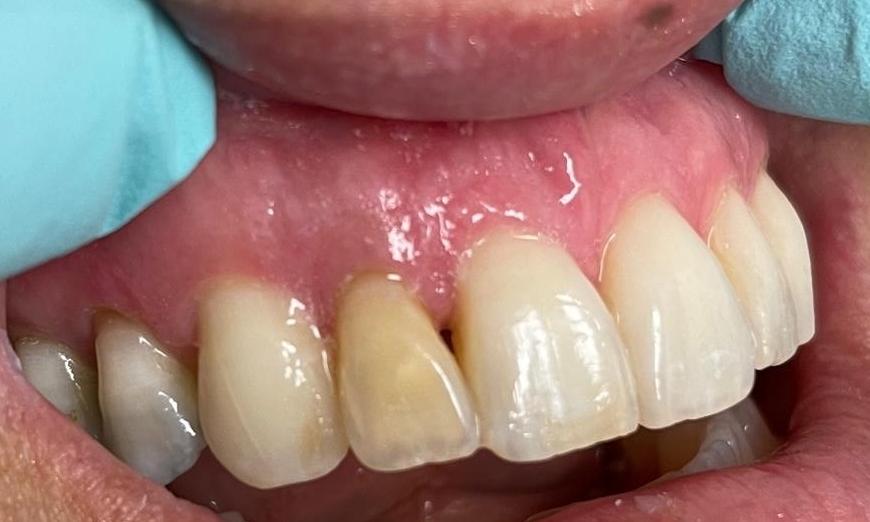

In this case, the patient's tooth #7 had a previous root canal and was darker and did not match the adjacent teeth.  A full coverage all ceramic crown was used to cover the tooth and match the shade to the adjacent teeth